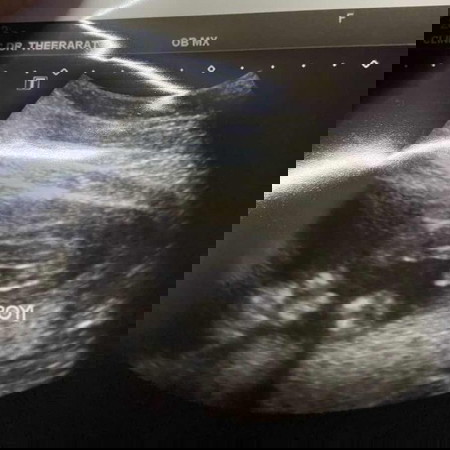

ลูกชายคนแรกค่ะ👶🏻

แม่ๆบ้านไหนซาวค์แล้วรู้เพศน้องกันบ้างแล้วค่ะมาอวดน้องกันหน่อยบ้านนี้ลูกชายเต็มจอเลยค้าา👶🏻😂💕💜#ทีมสิงหาคม#ลูกชายคนแรก#ท้องแรกคะ

บ้านนี้ส่งเข้าประกวดค่ะ สายชอบโชว์ ลูกชายคนแรก กำหนด 6 ส.ค. ค่ะ

บ้านนี้ท้องเเรกผู้ชายค่ะ เดือนสิงหา👶🏻

ท้องแรก ลูกชายเหมือนกันจ้า กำหนดคลอด 12 สค